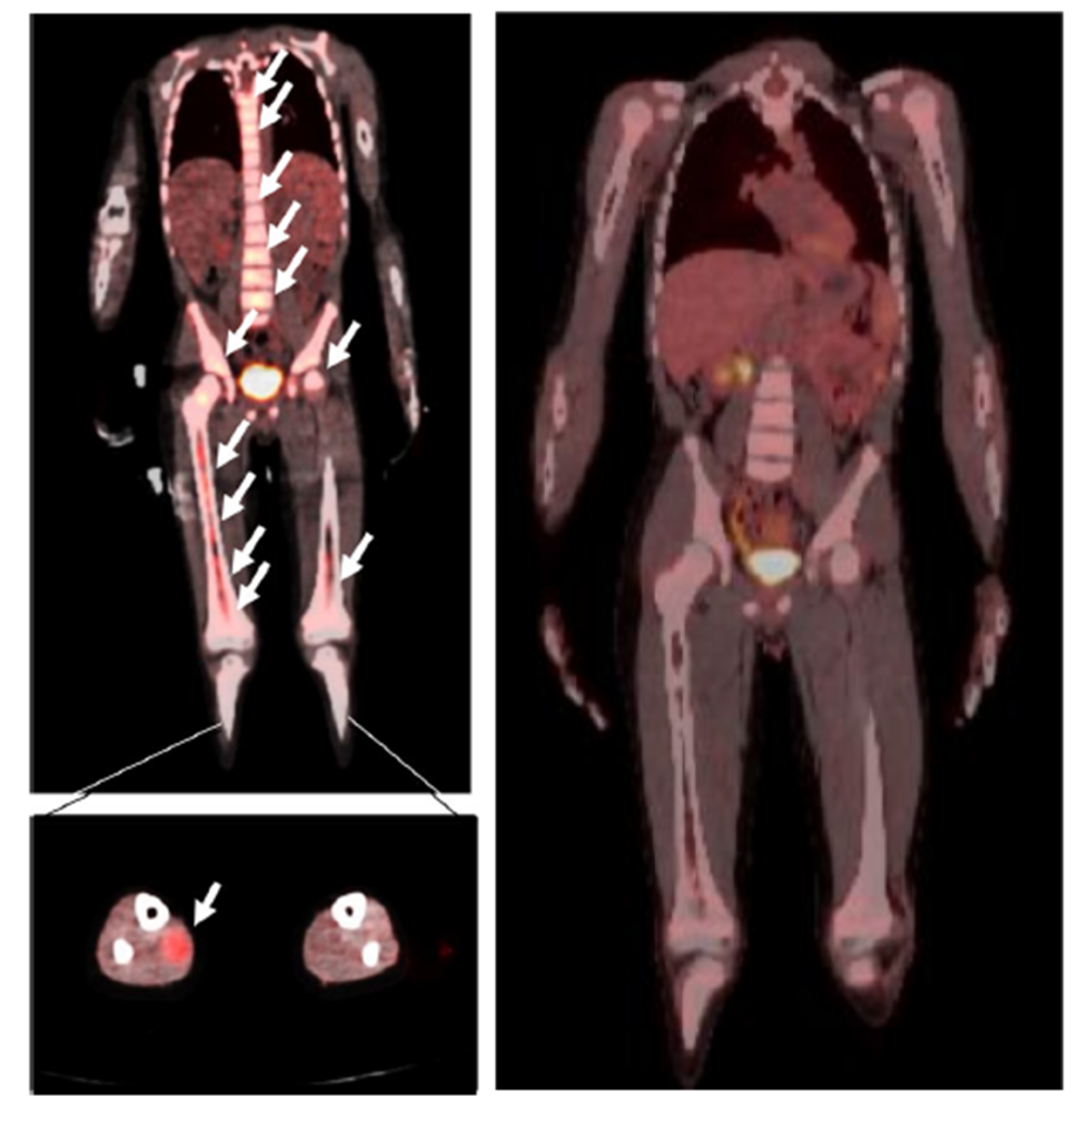

横纹肌肉瘤是儿童中最常见的软组织恶性肿瘤,虽然总体生存率在70%以上,但晚期转移性的横纹肌肉瘤生存率一直不太理想,很容易复发。 在历经初治化疗和放疗后,...